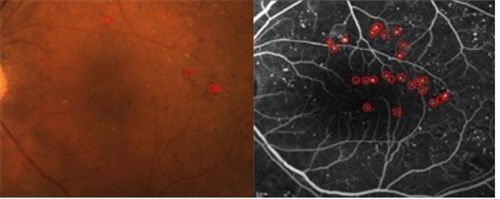

강남세브란스병원 안과 변석호 교수팀은 빛간섭단층촬영을 통해 당뇨황반부종의 직접적인 원인이 되는 미세혈관류를 찾아 선택적으로 응고시키는 치료법을 개발했다.

기존에는 일정 범위 내의 모든 미세혈관류를 레이저로 응고했으나 선택적 황반 국소 레이저 치료는 응고하는 미세혈관류를 최소화해 부작용을 줄였다는 것이 연구팀의 설명이다.

이는 치료하는 미세혈관류의 개수가 줄었기 때문인데 선택적 레이저 치료군에서는 평균 5.6±4.0개의 미세혈관류를 치료한 반면 기존 치료군에서는 16.3±11.8개의 미세혈관류를 치료해 큰 차이를 보였다.